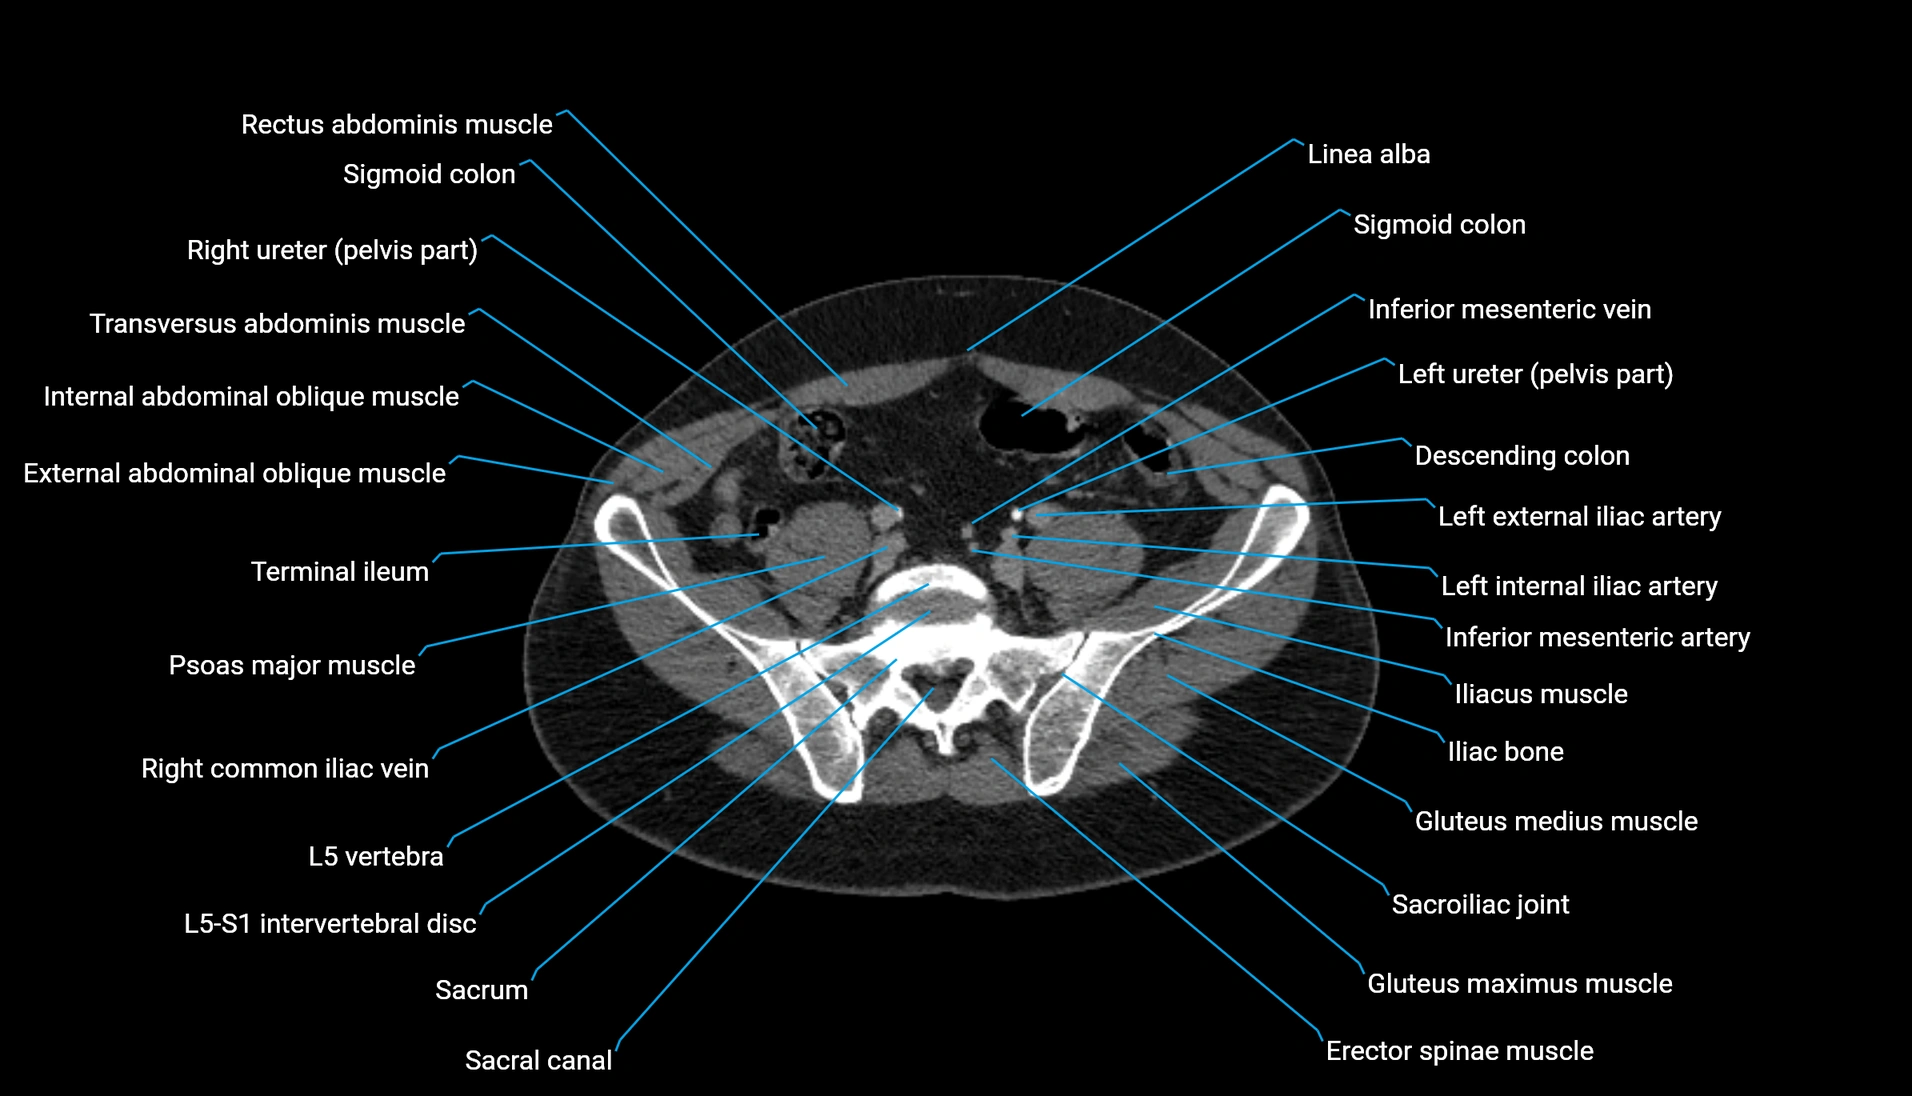

CT Appearance

Non-contrast CT:

-

Demonstrates cortical bone of acetabular rim in excellent detail

Detects fractures, dysplasia, retroversion, or bony overcoverage (pincer impingement)

3D reconstructions used in preoperative hip surgery planning

CT image